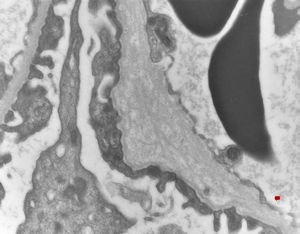

M,17y. | Alport syndrome - split and laminated basement membranes